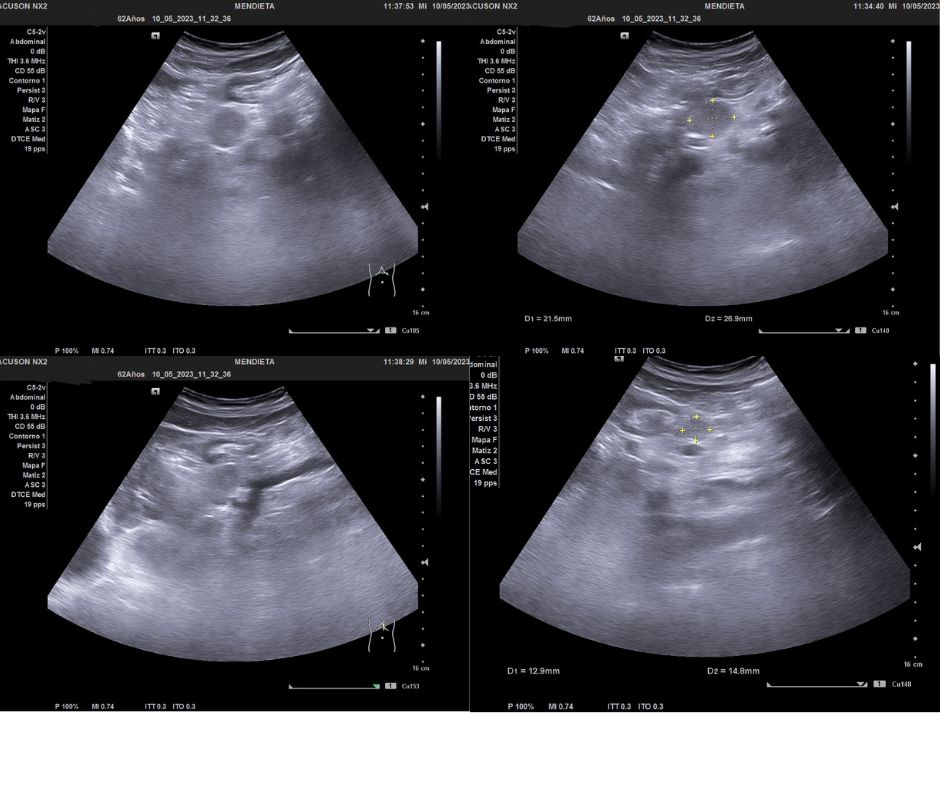

Ecografía clínica abdominal: Dos imágenes hipo/isoecogénicas a nivel de cabeza de páncreas redondeadas que no captan al Doppler color.